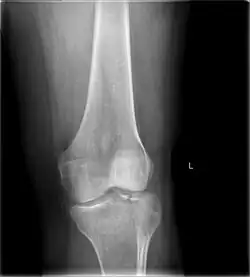

A tibial plateau fracture is a break of the upper part of the tibia (shinbone) that involves the knee joint.[1] This could involve the medial, lateral, central, or bicondylar (medial and lateral).[3] Symptoms include pain, swelling, and a decreased ability to move the knee.[1] People are generally unable to walk.[2] Complication may include injury to the artery or nerve, arthritis, and compartment syndrome.[1]